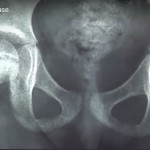

Herring (Lateral Pillar) Classification

This classification is based on the preservation of the lateral pillar of the femoral head epiphysis on anteroposterior radiographs during the fragmentation stage.

Type A

- Lateral pillar height: 100% preserved (no loss of height).

- Femoral head: Maintains normal height and structure.

- Prognosis: Excellent outcome.

Type B

- Lateral pillar height: More than 50% of the original height is maintained.

- Femoral head: Some collapse but lateral pillar is largely preserved.

- Prognosis: Good to fair outcome.

Type B/C Border Group (Modification)

- Introduced in the modified Herring classification.

- Features are intermediate between Type B and Type C.

- Lateral pillar: Around 50% height remaining, but with narrowing or early collapse.

- Prognosis: Variable; worse than B but better than C.

Type C

- Lateral pillar height: Less than 50% preserved (more than half lost).

- Femoral head: Severe collapse of the lateral pillar.

- Prognosis: Poor outcome, high risk of deformity and early osteoarthritis.